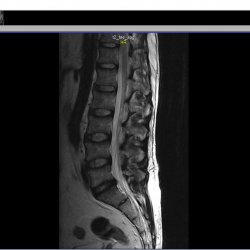

Здравствуйте. Постоянная боль в пояснице справа. Есть протрузия нижнего диска,  врач говорит, что она не должна болеть т.к. маленькая. Листая снимки заметил на соседнем диске какяю-то вертикальная полоса и темное пятно при пролистывании. Это норма или что-то ещё?